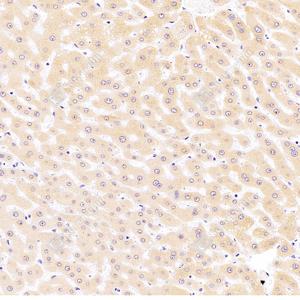

IHC检测CYPIVF11蛋白(货号 GB112710). 样品: 人肝, 4%多聚甲醛 (货号G1101) 固定12-24小时. 抗原修复: 柠檬酸抗原修复液(干粉, pH 6.0) (G1201), 98℃, 20分钟. —抗: 1: 1800稀释, 4℃ 孵育过夜. 二抗: HRP标记山羊抗兔IgG (H+L) (货号GB23303), 1: 200稀释, 室温孵育1小时. |